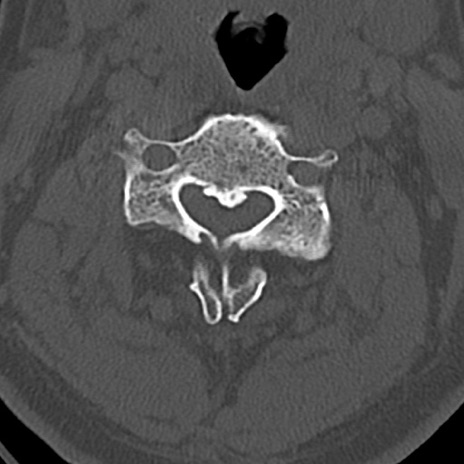

頚椎CT

横断像